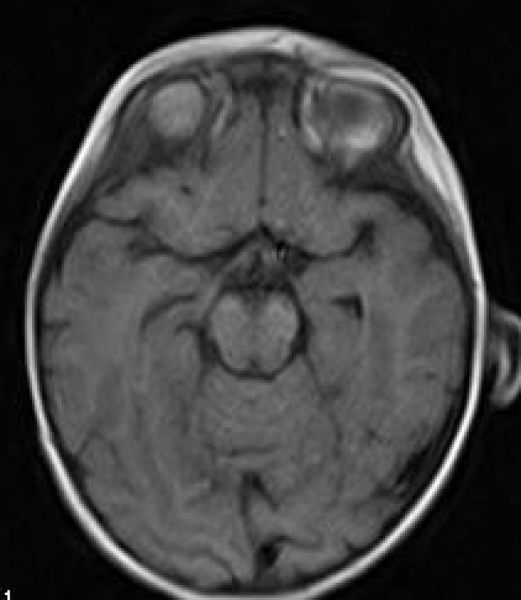

Специальные исследования

Для подтверждения диагноза Галлервордена-Шпатца и исключения других заболеваний проводятся специальные исследования, такие как:

- Нейрофизиологические исследования. Они включают в себя электромиографию (ЭМГ), электроэнцефалографию (ЭЭГ) и другие методы, которые позволяют оценить работу мышц, нервной и электрической активности мозга. Эти исследования могут помочь выявить нарушения в работе нервной системы и подтвердить диагноз.

Все эти исследования в комплексе помогают определить диагноз Галлервордена-Шпатца и оценить степень его проявления у пациента, что в свою очередь позволяет разработать индивидуальный план лечения и прогнозировать дальнейший ход заболевания.